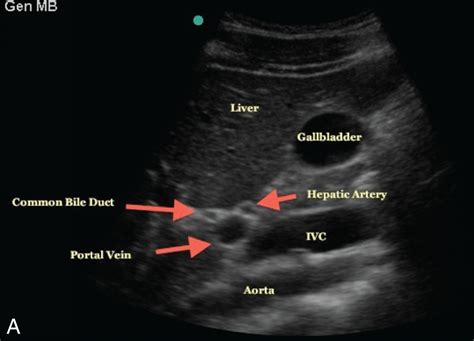

The Hepatic Artery Common arises from the celiac trunk, which is the first major branch of the abdominal aorta. From this origin, it travels a short distance before bifurcating into two major terminal branches: the proper hepatic artery and the gastroduodenal artery. Its placement is strategic, situated deep within the upper abdomen and behind the lesser omentum, making it a focal point during abdominal surgeries and interventional radiology procedures.

The liver is unique because it receives a dual blood supply: approximately 75% from the portal vein (which is nutrient-rich but deoxygenated) and 25% from the Hepatic Artery Common system. This arterial inflow is crucial because it provides the highly oxygenated blood necessary for the liver’s intense metabolic activities. Without this constant supply, the liver cells, or hepatocytes, would struggle to maintain energy balance and perform detoxification functions.

Because the Hepatic Artery Common is central to visceral perfusion, it is a primary area of concern in various medical scenarios, ranging from trauma to localized tumor management. When issues arise, such as an aneurysm, stenosis, or thrombosis, diagnostic imaging becomes the cornerstone of treatment planning. Physicians typically rely on advanced modalities to visualize this vessel clearly.

Doppler Ultrasound First-line assessment for blood flow velocity and direction.